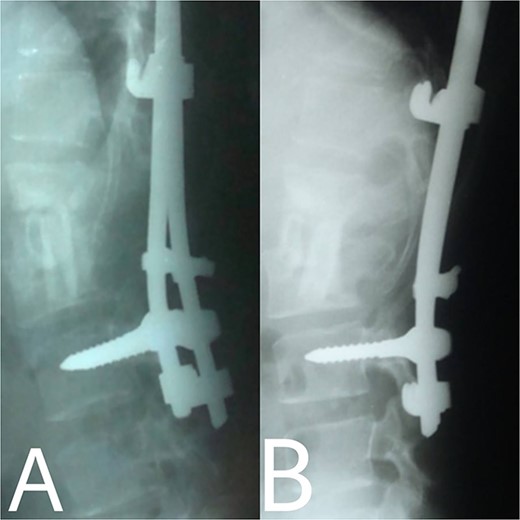

A 24-year-old farmer female was admitted to the Department of Neurosurgery with low back pain, no fever, cough, motor deficit, or any symptoms. Medical, surgical, family histories and physical examinations were unremarkable. The laboratory findings showed a white cell count of 9.8 × 103/μL, C-reactive protein concentrations of 20, erythrocyte sedimentation rate of 50 mm/1 h, 90 mm/2 h and tuberculin skin test was positive. X-ray films showed the collapse of the L1, L2 vertebrae, and L1–2 intervertebral space (Fig. 1). An abscess was observed at the L1–L2 vertebral level in lumbar magnetic resonance imaging (MRI) (Fig. 2). Chest X-rays and Sputum smear were negative. The patient was treated with anti-TB treatment (Isoniazid, Rifampicin, Ethambutol, Pyrazinamide) due to spinal TB findings on MRI (Fig. 3). After 40 days, the patient was diagnosed with grade 1/5 lower limb weakness, and bladder and bowel dysfunction, with no impairment in sensation, which predicts spinal infection. MRI confirmed these abnormalities and showed typical findings such as vertebral endplate destruction, bone marrow and disk signal abnormalities, and paravertebral or epidural abscesses (Fig. 3). Due to clinical manifestations and MRI spinal TB findings (Fig. 3), the patient underwent surgical debridement, interbody fusion and internal fixation with fibular autografting and supplemental posterior spinal stabilisation using a posterior-only approach. On post-operative follow-up, the treatment continued for 9 months, in addition to physical therapy for lower limb weakness. In the end, the patient returned to full motion with grade 5/5 in the lower limb, normal sensation, and no bladder or bowel incontinence. No recurrence was observed in the grafting area. Radiologically 2, 6 and 12 months, 14 years’ post-operation, the patient had achieved full bony graft spinal fusion (Figs 4–6).

(A, B) Complete bony incorporation between the implanted fibular autograft and host vertebral body was noted on the lateral radiograph 1, and 14 years later.

Even though a spinal epidural abscess is a rare infectious situation, its incidence is increasing due to risk factors such as chronic illnesses, immunodeficiency states and drug abuse. MRI is an effective diagnostic test for spinal infection and to differentiate between TB and pyogenic spondylitis. It is difficult to determine the diagnosis when there are atypical manifestations of infectious spondylitis. However, in our case, MRI demonstrated the typical finding such as the compression of the spinal cord by the two vertebral endplates destruction, the epidural abscess, the disk signal and bone marrow abnormalities. Conservative therapy is the basis of spinal TB treatment. This approach is insufficient in some cases that require surgical interventions [4]. When indicated, delayed surgical management may lead to a bad prognosis [5]. As in our case, the paraparesis developed after 40 days of TB drug administration. These aspects necessitated surgical procedures to prevent further spinal cord compression [6]. Surgical techniques included posterior approach decompression, abscess resection, bone grafting and instrumentations. Spinal TB primarily impacts the anterior elements due to its blood supply profusion. Hence, the conventional approach has long been to use the anterior approach in spinal TB treatment [6, 7]. A prospective study has shown that the anterior approach has good results in a minimum period of a 3-year follow-up. Also, Ge et al [8]. reported a case of spinal TB involving the L1 vertebra with a massive paravertebral abscess. They used the anterior approach in the decompression and grafting with posterior instrumentations and their results were satisfactory. However, in recent years, the posterior approach proved its advantages, including its familiarity, enough space for an adequate debridement of the focal lesion, in addition to less surgical invasion. Both approaches lead to reduced operation duration and fewer rates of complications [9]. On the other hand, the anterior approach has its risks, such as abdominal visceral injury, and neural and vascular injuries. Moreover, spinal instability may occur [10]. As for grafting, we used an autogenous bone graft from the fibula for osseous loss, which may be considered a golden standard, because of its immune correspondence and osteoinductive capability [4]. There are considerations about inserting a bone graft in an infected site, like the surrounding tissue’s capability to provide the biological background for recovery. The presence of biomechanical stability enables biological reactions to enhance bone ingrowth [11]. Bansal et al. reported the fibular strut graft efficacy along with cancellous graft in an anterior approach and without instrumentations [12]. Singh et al. also showed the same results but without cancellous graft [7]. In our case, the bone graft was supported with the posterior (T10–L3) hooks combination and screws. Spinal cord decompression is the priority. Besides, the infected extracted tissues had to be replaced with another component for the spinal column stability. The X-ray showed a successful fusion post-operation. The medication was administered for 9 months to prevent the recurrence of the infection [13]. After treatment, the muscle strength became 5/5 up from the pre-operative 1/5. Within 14 years of follow-up, the X-ray demonstrated a good bone fusion and the patient’s status was good (Fig. 6). Minimally invasive spinal surgery (MISS) has been used increasingly over the past two decades [14]. MISS is performed using smaller incisions instead of traditional open approaches to accomplish spine surgical operations. MISS includes spinal endoscopy and robotics, which has improved the accuracy of instrumentation placement and virtual/augmented reality that has been very helpful for practicing surgical skills without patients. These techniques decreased the sedation requirements, blood loss and hospitalisation time [15]. In conclusion, early diagnosis of TB spondylitis with proper treatment and surgical intervention immediately after a neurological deficit can protect the patients from the chronic spinal deformity. The posterior approach was sufficient and effective in our case. However, the surgical procedure should be planned on a case-by-case basis. Fibular graft and instrumentations were effective, although they were inserted on an infected background.